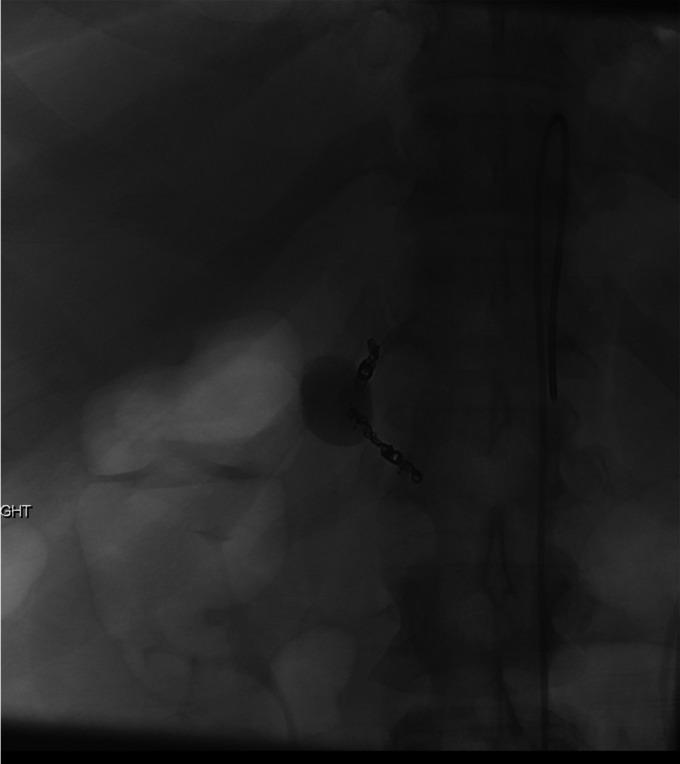

成功微创治疗导致肝外胆管受压的胃十二指肠动脉假性动脉瘤

Successful Minimally Invasive Management of a Gastroduodenal Artery Pseudoaneurysm Causing Extrinsic Bile Duct Compression.

Gastroduodenal artery (GDA) pseudoaneurysms are rare clinical entities that typically develop in the setting of chronic inflammation of the pancreas, although idiopathic pseudoaneurysms can occur. Although GDA pseudoaneurysms carry the risk of rupture with resultant hemorrhage, they seldom are reported to cause biliary obstruction. We report a unique case of biliary obstruction secondary to extrinsic compression of the bile duct by a GDA pseudoaneurysm successfully managed by nonoperative means.

摘要

胃十二指肠动脉(GDA)假性动脉瘤是一种罕见的临床病症,通常在胰腺慢性炎症的背景下发生,不过也可能出现特发性假性动脉瘤。尽管GDA假性动脉瘤有破裂并导致出血的风险,但很少有报道称其会引起胆管梗阻。我们报告了一例独特的病例,该病例为GDA假性动脉瘤对胆管造成外部压迫继发胆管梗阻,通过非手术方法成功治愈。